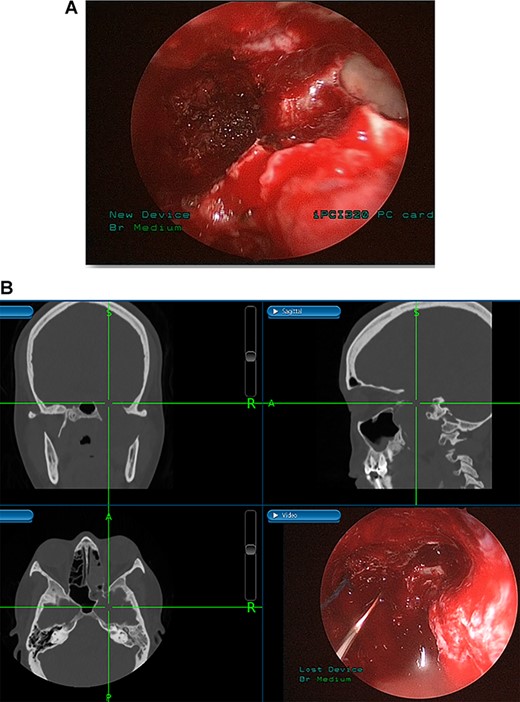

(A) Endoscopic view of the final surgical cavity after tumor removal. (B) Image-guided tumor removal from cavernous carotid artery.

The patient underwent an image-guided endonasal endoscopic tumor removal starting by endoscopic medial and posterior walls maxillectomies to control the tumor removal from the lateral sphenoid sinus and the infratemporal fossa after cauterization of the maxillary artery and sphenopalatine artery branches feeding the tumor. The tumor was dissected and removed from the cavernous (Fig. 3A) and petrous carotid artery in the middle cranial fossa (Fig. 3B). The middle cranial fossa’s dura was intact during the tumor removal (Fig. 3C). All the steps of tumor removal were controlled and monitored under image-guided navigation for accurate localization of tumor removal and avoidance of violation to the middle cranial fossa’s dura, or the brain, and the internal carotid artery in its cavernous and petrous segments (Fig. 4a and b).